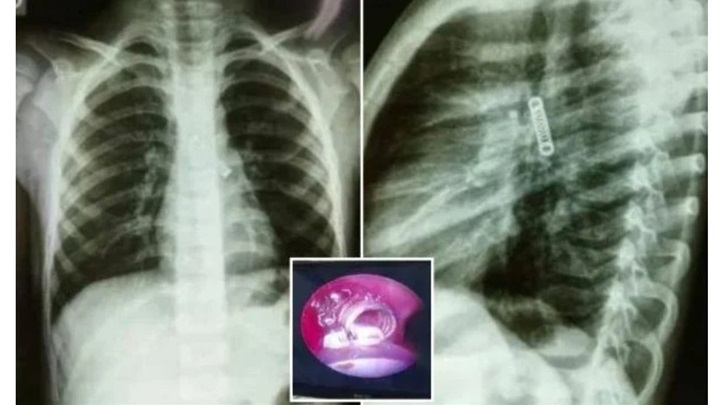

Dok su liječnici obavljali opsežne provjere kako bi otkrili što se događa i zašto kašalj ne prestaje mjesecima, pronašli su metalni predmet u dječakovom lijevom plućnom krilu.

Rentgenske snimke su, naime, otkrile da dječak ima metalnu oprugu u plućima! Prebačen je u Nacionalni institut za respiratorne bolesti na hitno liječenje.

Ondje je operiran i uspješno mu je uklonjena metalna opruga.

Dr. Carlos Morinigo je izjavio kako je operativni postupak bio kompliciran zbog vremena tijekom kojeg je strano tijelo ostalo zaglavljeno u dječakovim plućima, kao i štete koju je prouzročilo u tom razdoblju.

Unatoč tome što je prouzročilo, kako su liječnici ustvrdili, "vjerojatno smanjenje kapaciteta pluća", dr. Morinigo je izrazio očekivanje da će se stanje vjerojatno poboljšati kako dječak bude rastao.